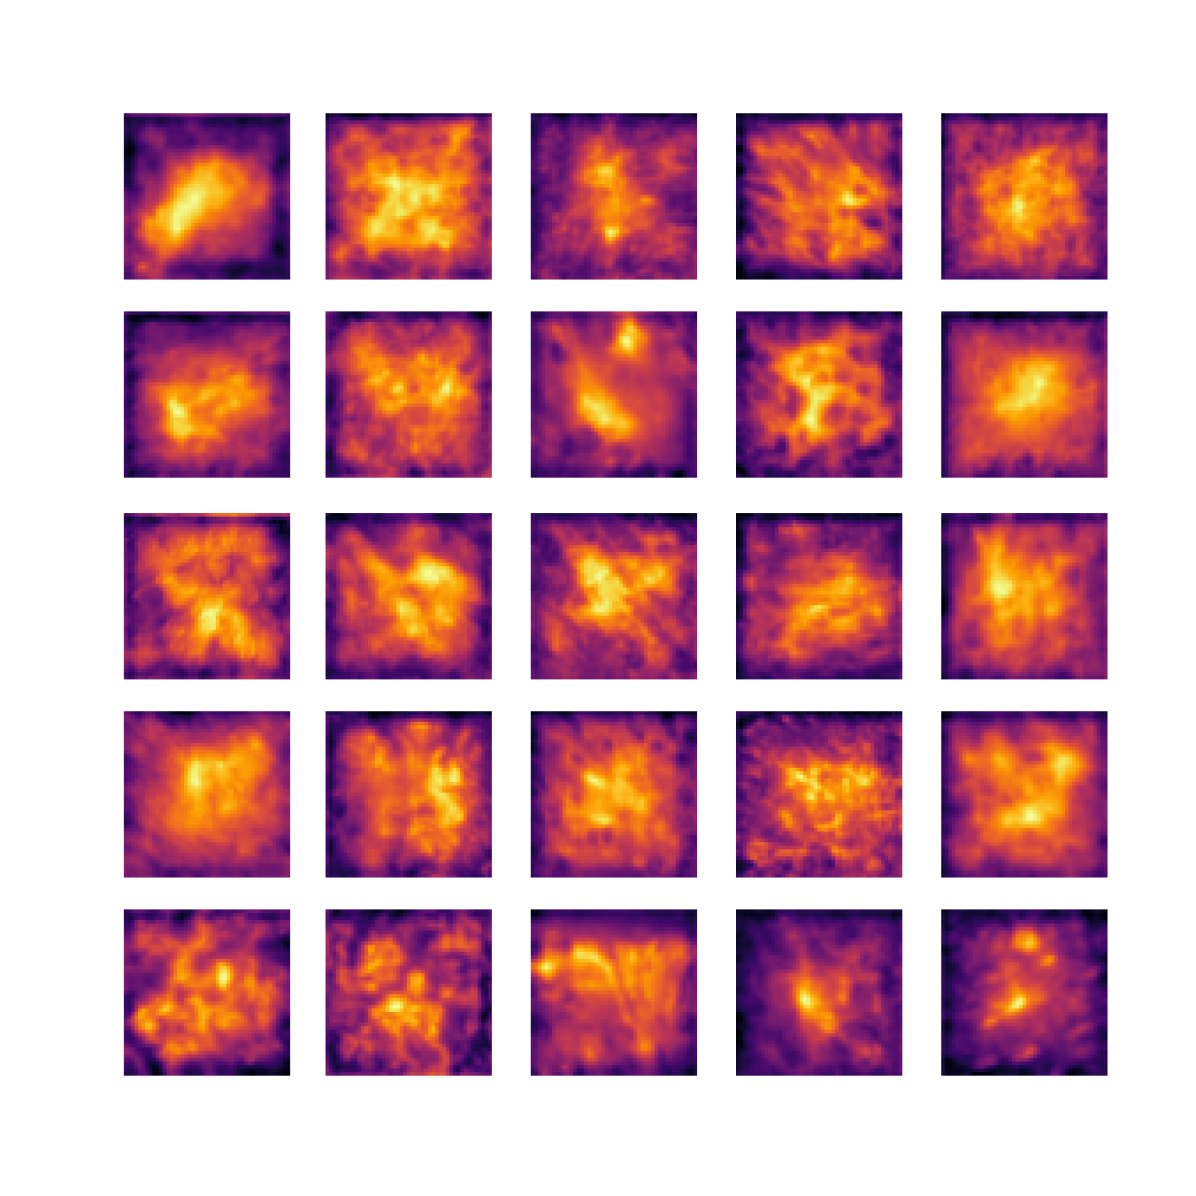

We also analyse the activation maps for each model using GradCAM as described in section S3. This offers more insight into the areas of the image which are contributing most heavily to the models’ representations. In Figure 4(b) we present some representative examples, however, a larger selection which was chosen at random is presented in Figures S10 to S25. The larger selection makes it easier to see the emergent patterns, including that privileged Siamese models tend to mainly identify features which are strongly present in both inputs, while unprivileged Siamese models tend to learn more diffuse features that are not specific to one cell phenotype or image region. TriDeNT ♆ incorporates both sets of features, learning both features specific to the privileged data and more the general features associated with unprivileged Siamese networks.

We can see in Figure 4(b) panel A that for ERG, the privileged Siamese model focuses almost exclusively on any nuclei which could be endothelial cells. As there are very few endothelial cells in the dataset, it could be an effective strategy to identify anything that could potentially be an endothelial cell to minimise the difference between the representations of the H&E model and the IF mask model. In the corresponding unprivileged Siamese image, we see that the model identifies some of these nuclei, albeit less strongly, but also focuses heavily on the other tissue and even the background, while strongly fixating on two spots of debris in the center of the image. This model has less ‘incentive’ to learn the weak features related to endothelial cells as these occur rarely and are not easy to detect, while more generic strong features such as the presence of connective tissue and the prevalence of background are more common and predictable from augmented images. We see that TriDeNT ♆ combines these two feature sets, strongly identifying nuclei while also identifying the connective tissue.

In panel C we see a similar pattern, with the privileged Siamese model fixating solely on the nuclei, while the TriDeNT ♆ model takes a more balanced approach. The unprivileged Siamese model appears to focus on a single cluster of nuclei while neglecting others, and similarly identifies an area of fibroblasts with its distinctive pattern but does not others.

In contrast to panels A and C which represent models with poor privileged Siamese results, panels B and D represent models whose privileged Siamese results were comparable to both TriDeNT ♆ and even the supervised baseline. It is therefore interesting to note that there are far more similarities between the privileged Siamese and TriDeNT ♆ models in both cases. Particularly in panel B, TriDeNT ♆ and the privileged Siamese model return virtually identical heatmaps, with both strongly identifying epithelial nuclei and neglecting the same areas of connective tissue. The unprivileged model in this case appears to focus solely on the centre of the image, giving a significantly different heatmap to the other panels.

Panel D again shows the previous pattern, with the privileged Siamese model identifying the features strongly present in the privileged data – fibroblasts – while neglecting the nuclei present. TriDeNT ♆ also strongly identifies the connective tissue, but, unlike the privileged Siamese model, does not completely neglect the nuclei. The unprivileged Siamese model primarily identifies background, and does not appear to identify the nuclei in this example.